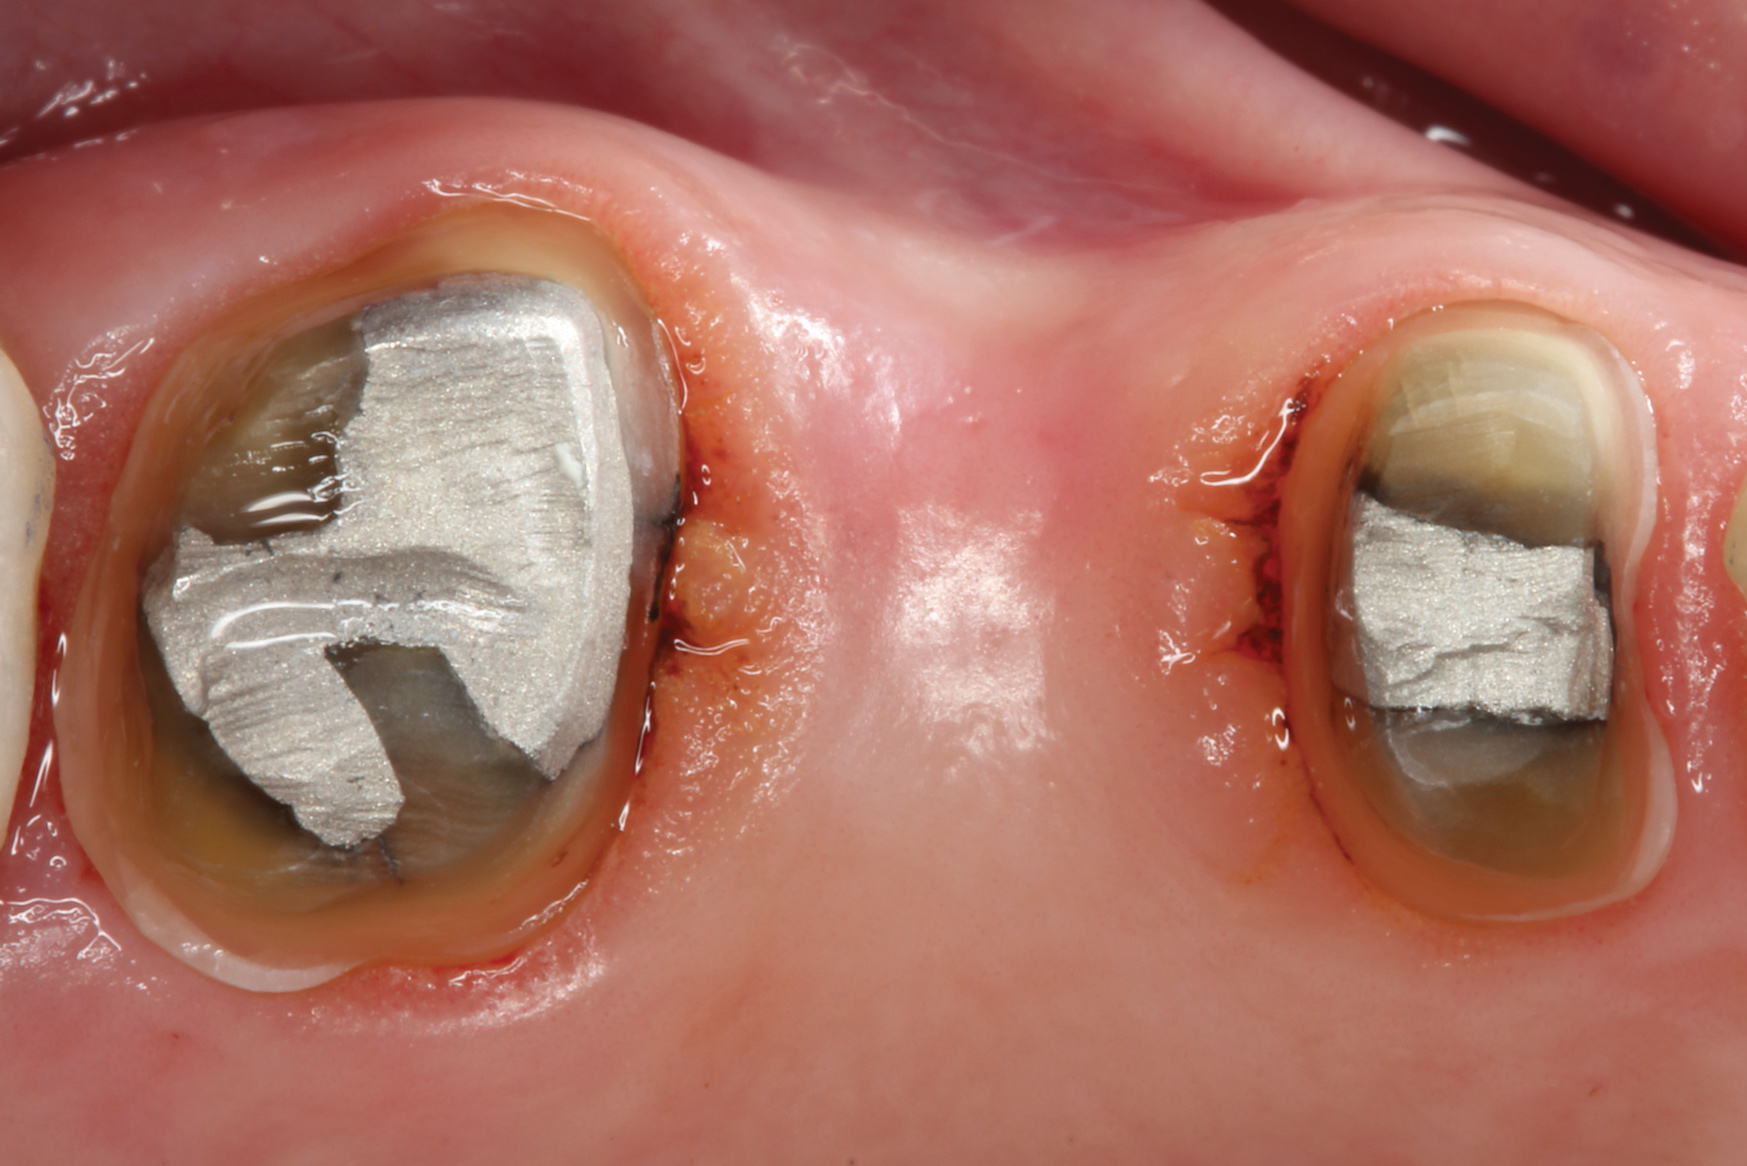

With these limitations acknowledged, visual inspection of tooth preparations after air abrasion reveals that this modality is effective in removing remnant restorative materials, stains, and temporary cement, leaving a clean, matte surface for bonding (Figure 11 through Figure 14). Air abrasion also can smooth the internal aspects of a cavity preparation to help enable better adaptation of the restorative material (Figure 15 and Figure 16). The technique-sensitive nature of adhesive bonding may justify this extra procedure to ensure a clean, smooth preparation.

Fig 13. Crown preparations with temporary cement remnants prior to air abrasion (Fig 13) and after air abrasion (Fig 14) (case by Mohammed Badahman, DDS).

Fig 14. Crown preparations with temporary cement remnants prior to air abrasion (Fig 13) and after air abrasion (Fig 14) (case by Mohammed Badahman, DDS).

Figure 14